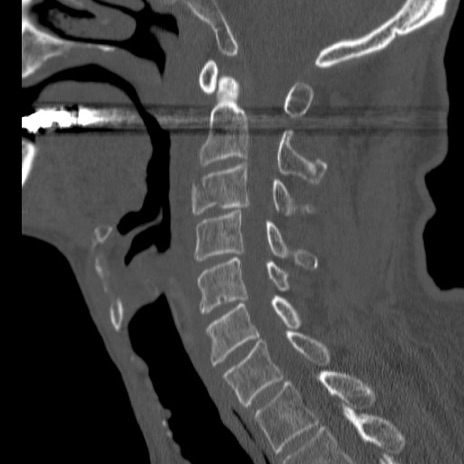

症例46 頚椎CT(矢状断像)

【症例】80歳代男性

【主訴】両側頚部〜上肢のしびれ

【現病歴】昨日、自宅内で転倒、その後より上記症状あり。意識障害なし。

【身体所見】両側上肢のallodynia(熱痛覚過敏)あり。MMTおよびDTRは正確な所見取れず。両上肢の挙上はなんとか可能。

異常所見と診断は?